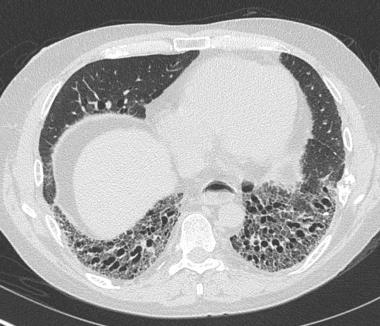

马赛克灌注,蜂窝肺2

图片尺寸756x470